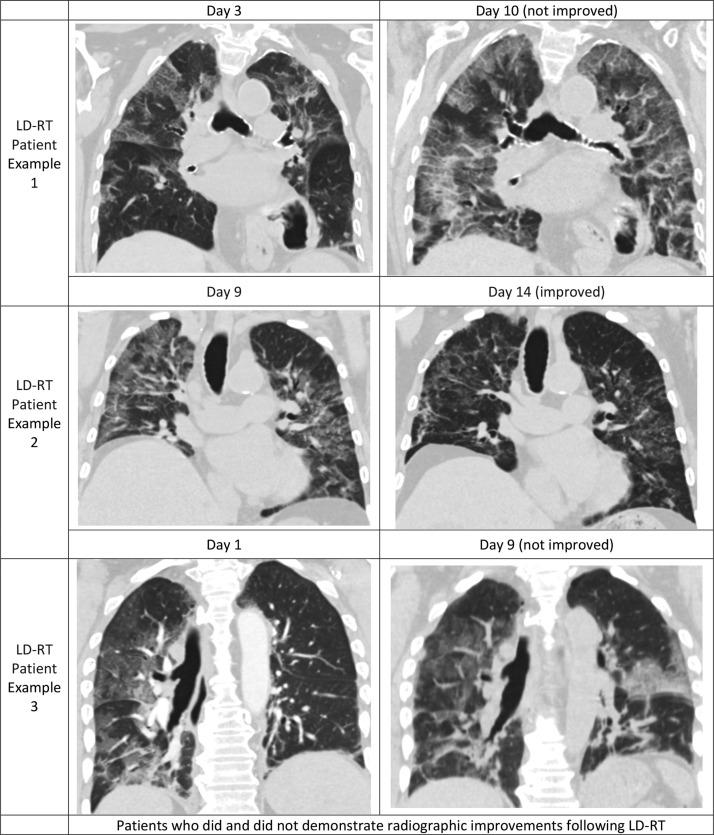

Of 40 patients evaluated, 20 received drug therapy combined with whole-lung LD-RT and 20 without LD-RT. Intubation rates were 14% with LD-RT compared to 32% without (p = 0.09). Intubation-free survival was 77% vs. 68% (p = 0.17). Biomarkers of inflammation (C-reactive protein, p = 0.02) and cardiac injury (creatine kinase, p < 0.01) declined following LD-RT compared to controls. Mean time febrile was 1.4 vs 3.3 days, respectively (p = 0.14). Significant differences in clinical recovery (7.5 vs. 7 days, p = 0.37) and radiographic improvement (p = 0.72) were not detected. On subset analysis, CRP decline following LD-RT was predictive of recovery without intubation compared to controls (0% vs. 31%, p = 0.04), freedom from prolonged hospitalizations (21+ days) (0% vs. 31%, p = 0.04), and decline in oxygenation burden (56% reduction, p = 0.06). CRP decline following 1st drug therapy was not similarly predictive of outcome in controls (p = 0.36).